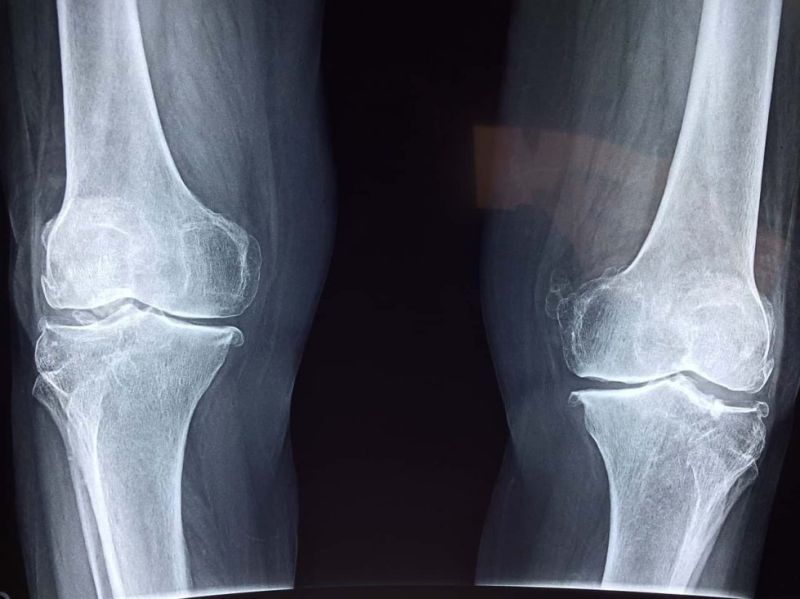

Другим источником звука являются напряженные связки, когда те соскальзывают с одной костной поверхности на другую. Медики называют этот звук крепитацией, его можно услышать или почувствовать в области колен во время подъема и спуска по лестнице.

Когда хрящевые поверхности сустава изнашиваются, в них образовываются неровности. В итоге кости перестают плавно скользить и сустав начинает хрустеть. Иногда возникновение хруста – предсказатель появления симптомов артроза.